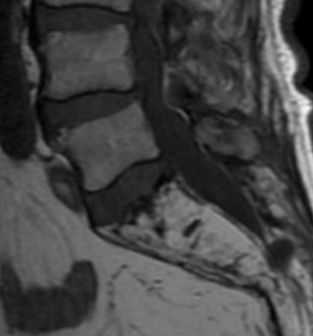

(Слева) Сагиттальный срез, Т1-ВИ шейно-грудного отдела позвоночника: признаки однородного усиления сигнала костного мозга грудных позвонков с достаточно хорошо выраженной переходной зоной этих изменений на уровне Т1-Т2, т. е. на уровне верхней границы области облучения.

(Справа) Сагиттальное Т1-ВИ с признаками гомогенной постлучевой жировой перестройки костного мозга грудных позвонков и четкими границами этих изменений, соответствующими границам области облучения.